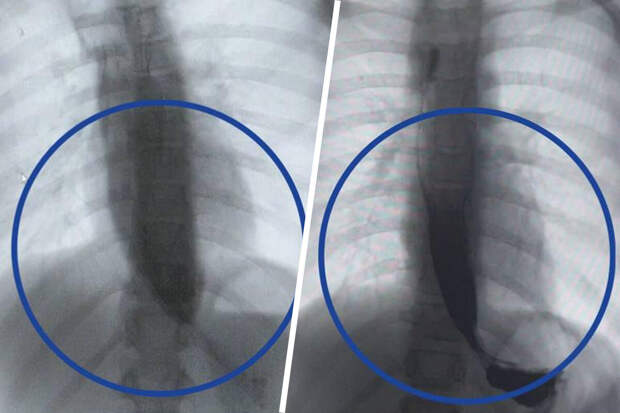

Медики рассказали, что пищевод пациентки из-за патологии был расширен до четырех сантиметров, при норме в семь - десять миллиметров.

Операция прошла успешно, что уже на следующий день показало контрастное исследование - пища стала беспрепятственно поступать в желудок.